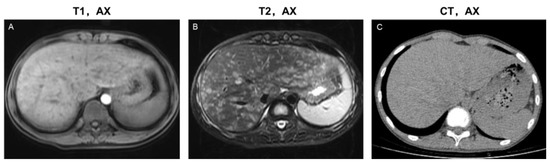

3.2. Image Phenotypes Based on Lesion Distribution

3.3.1. Parenchymal Lesions